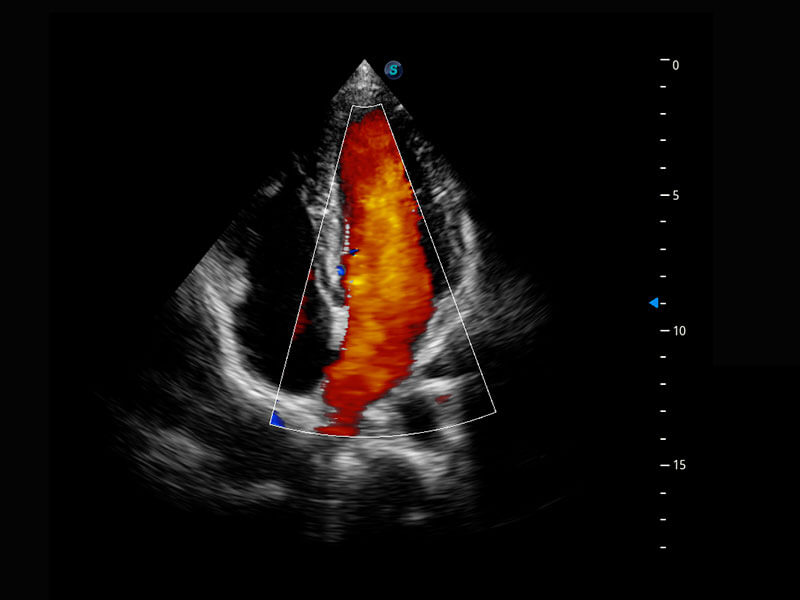

胎心筛查

P60搭载一系列胎儿心脏成像技术,实现精细的胎儿心脏评估。

• 四腔心血流

• 胎心容积成像